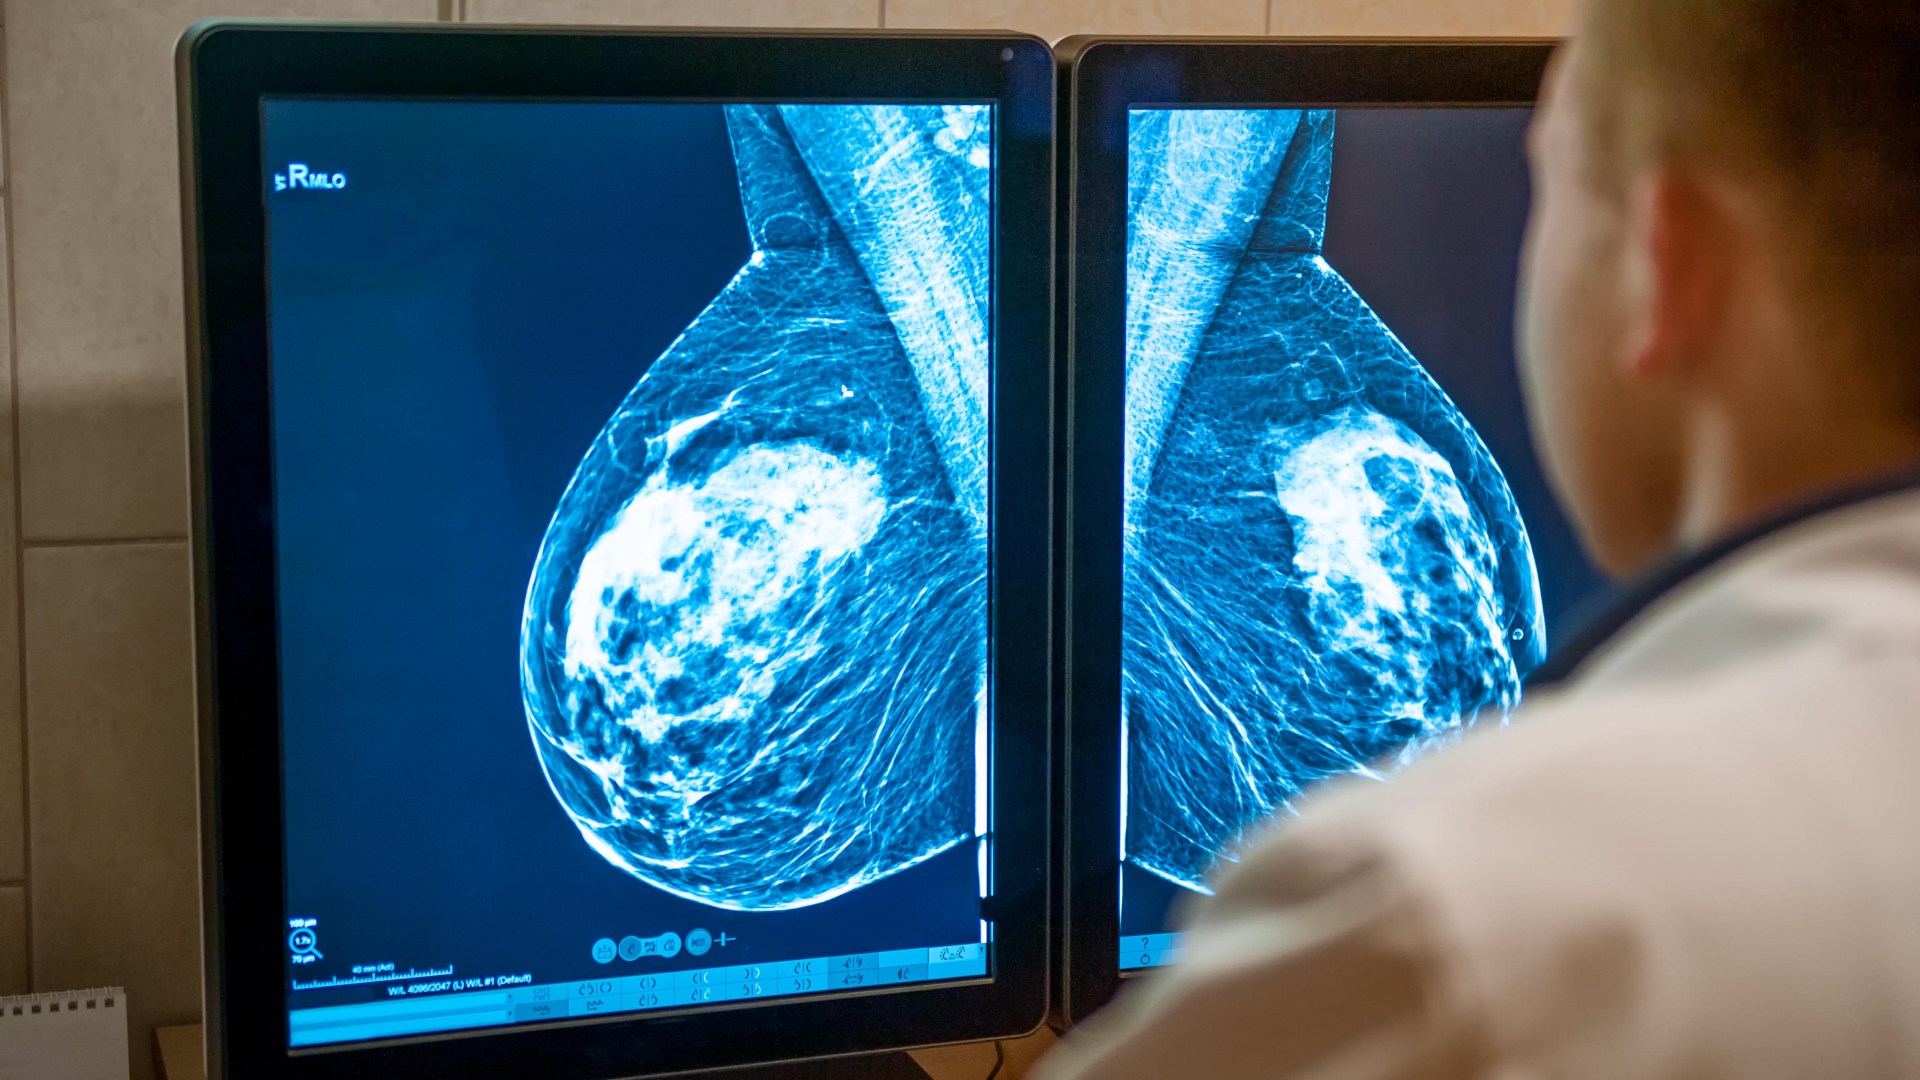

Cancer screening programs in England, while effective in detecting thousands of tumors annually, are facing a significant challenge due to low participation rates. Current data suggests that approximately 70% of eligible individuals take up the free screenings offered by the NHS, leaving a substantial number of potential cancers undiagnosed. Experts estimate that if participation were to reach 100%, an additional 7,000 cases of breast, bowel, and cervical cancers could be detected at an early stage each year, significantly improving the chances of successful treatment and survival. This underscores the crucial role of increased public awareness and engagement with these life-saving programs.

The declining coverage rates are a worrying trend, despite compelling evidence demonstrating the efficacy